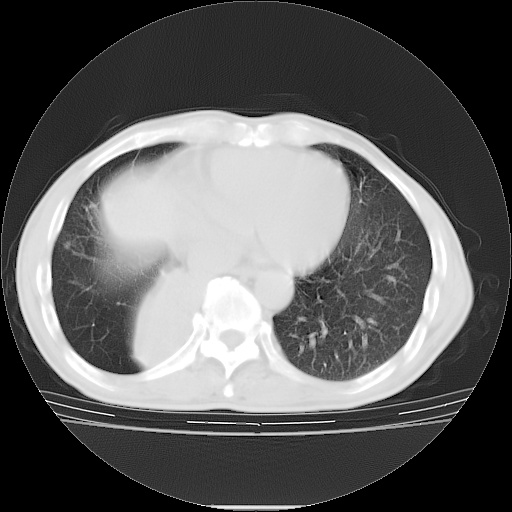

男性患者,63岁。右侧胸背部疼痛2月,加重一周。

考虑:右肺中央型肺癌并右肺下叶不张;两肺尖继发性肺结核。

还有----下叶不张   挺典型

右下肺中心型肺癌并肺不张

考虑右中心型肺癌并右下肺不张,肺及纵隔,左肋骨转移。

右肺下叶支气管狭窄闭塞,右下肺不张,气管前间隙淋巴结肿大,两上肺散在分部粟粒灶,沿肺血管支气管束分部,血管支气管束走形较为光滑。考虑右肺中心型肺癌合并肺不张,纵隔淋巴结转移,两上肺癌性淋巴管炎

右肺下叶中心性肺癌并纵隔淋巴结转移,左侧肋骨转移。双肺上叶继发性结核表现。

1)右肺下叶中心性肺癌并纵隔淋巴结转移,两肺转移,左侧肋骨转移。2)双肺上叶继发性结核。

右肺下叶中心性肺癌并纵隔淋巴结及两肺、左侧肋骨转移。双肺上叶继发性结核表现。